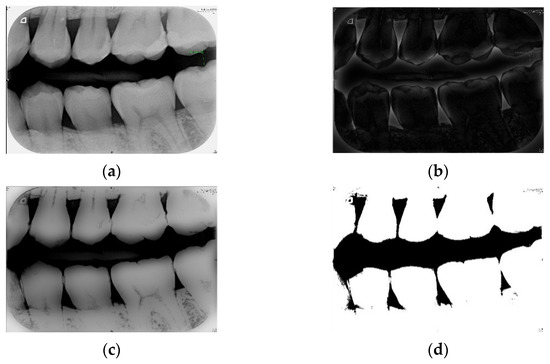

In this study, Otsu’s algorithm was adopted to select the threshold value. Its principle is to automatically find the threshold value for cluster-based images. The algorithm assumes that the image has a two-mode histogram (a histogram distinguished by foreground and background pixels). The optimal threshold that can separate the foreground and background pixels can be calculated by using the exhaust method in order to obtain the minimum number of variations in individual classes and the maximum number of between-class variations. According to the histogram obtained from different thresholds, the corresponding number of individual class and between-class variations is obtained, and the differences are compared [25,26]. The implementations are shown in Figure 2.

Figure 2.

(a) The bitewing film; (b) the filtered result of (a) using the Gaussian high-pass filter; (c) the result of (a) minus (b); (d) the result of (c) after the binarization.